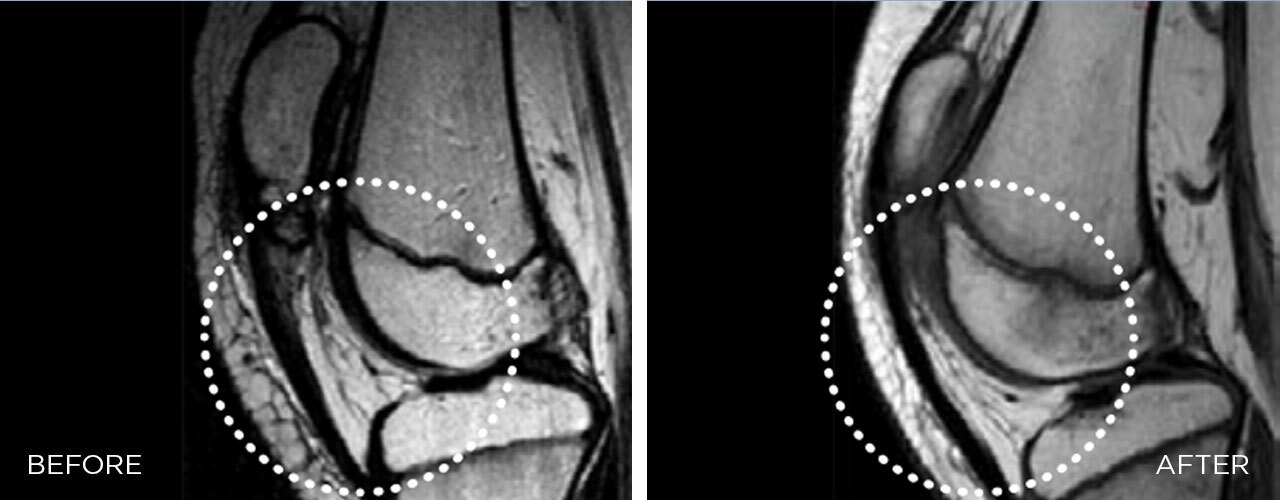

Calcification

Calcification -

Bone non-unions

Bone non-unions -

Mechanism of action

The focused shockwave causes deep cell stimulation that releases growth factors responsible for tissue regeneration and the initiation of healing processes in the damaged tissues.

It is a gold standard treatment for deep-lying tendinopathies, calcifications, and delayed bone healing conditions, such as pseudoarthrosis.